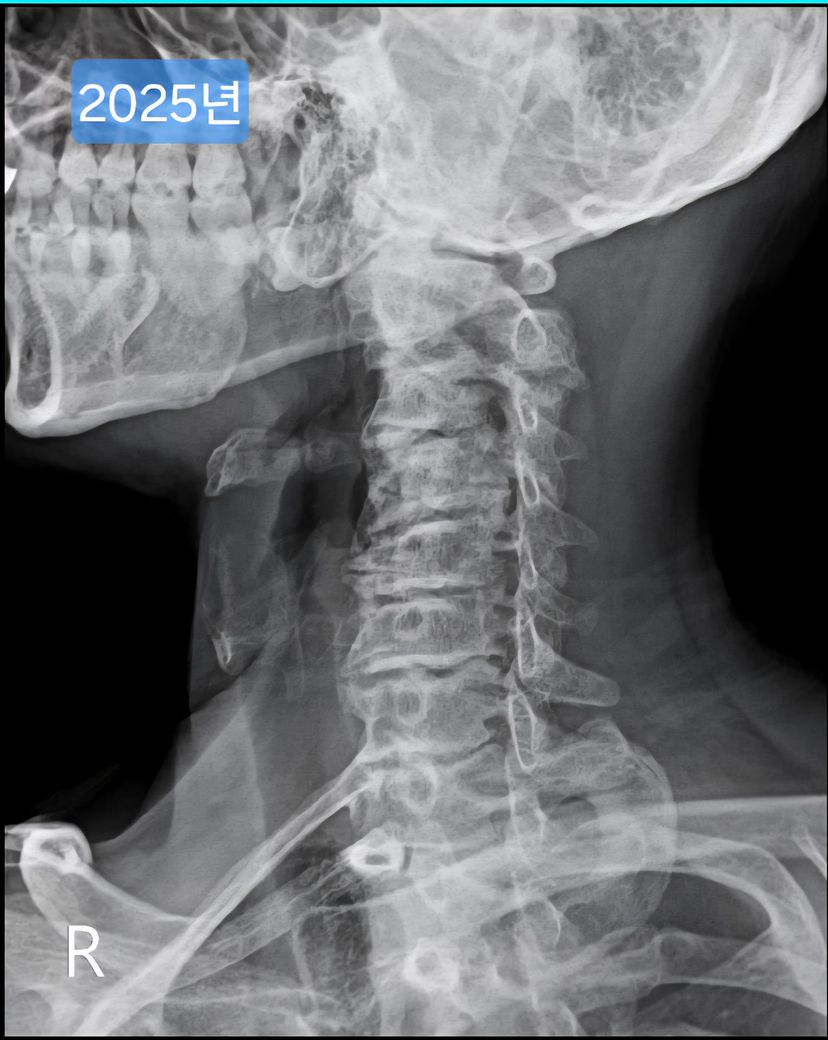

일자목, 경추사이 공간이 좁은 안좋은 형태의 목상태 입니다

다만 목의 경추 사이가 좁은것은 퇴행성에 가깝기에 바른 자세와 운동으론 제한이 될 수 있지만 일자목과 같은 목의 커브 감소는 약간은 회복이 가능하니 현재 상태를 정확히 확인 후 상태에 따른 적합한 운동법을 배우시길 추천드립니다^^